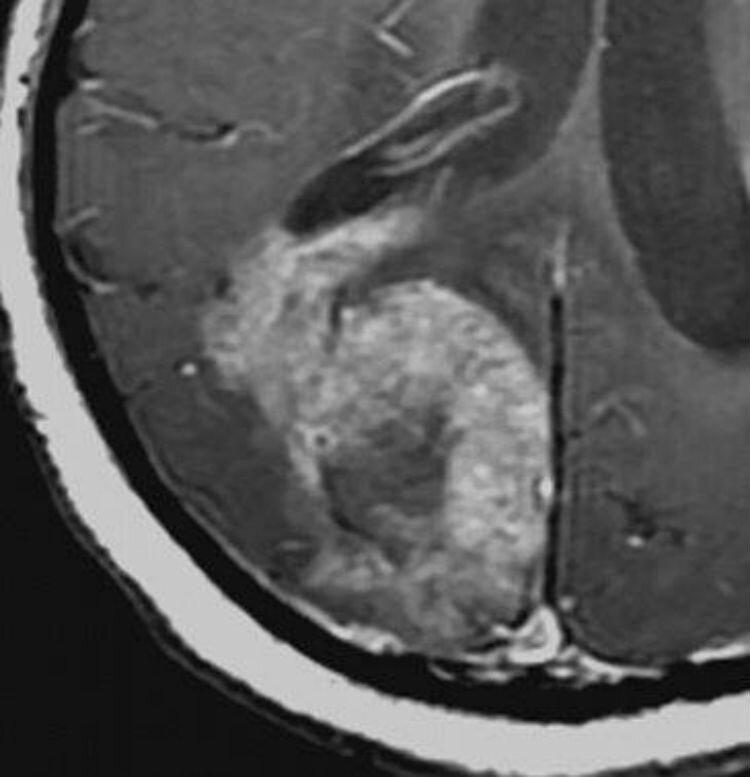

Редко когда научные публикации делаются без особой научной ценности — теоретической или практической. Тем не менее, в недавнем номере журнала World Neurosurgery два хирурга, Тарик Массуд и Александр Калнинш из Стэнфордского университета опубликовали просто клинический случай «очередной» глиобластомы. И нельзя ведь сказать, что публикация — бесполезна.

Credit: Tarik Massud

В статье, собственного текста которой — страничка, авторы публикуют глиобластому 46-летней пациентки, скончавшейся через три с половиной года после постановки диагноза. Увы, такая опухоль почти всегда смертельна. И публикация призвана подчеркнуть смертельность заболевания и привлечь внимание к разработке новых методов лечения.

Дело в том, что на МРТ опухоль очень напоминает по форме зайца, причем так, как его изображают в распространённых средневековых миниатюрах, где он часто выступает в роли убийцы рыцаря (вспомним фильм про Монти Пайтона и кролика-убийцу, сторожившего вход в пещеру Каербанног).

Авторы подчеркивают смертельность заболевания и призывают к максимальному освещению проблемы глиобластомы. Наш портал полностью поддерживает эту инициативу и уже опубликовал обзорную статью посвященную глиальным опухолям мозга вообще.